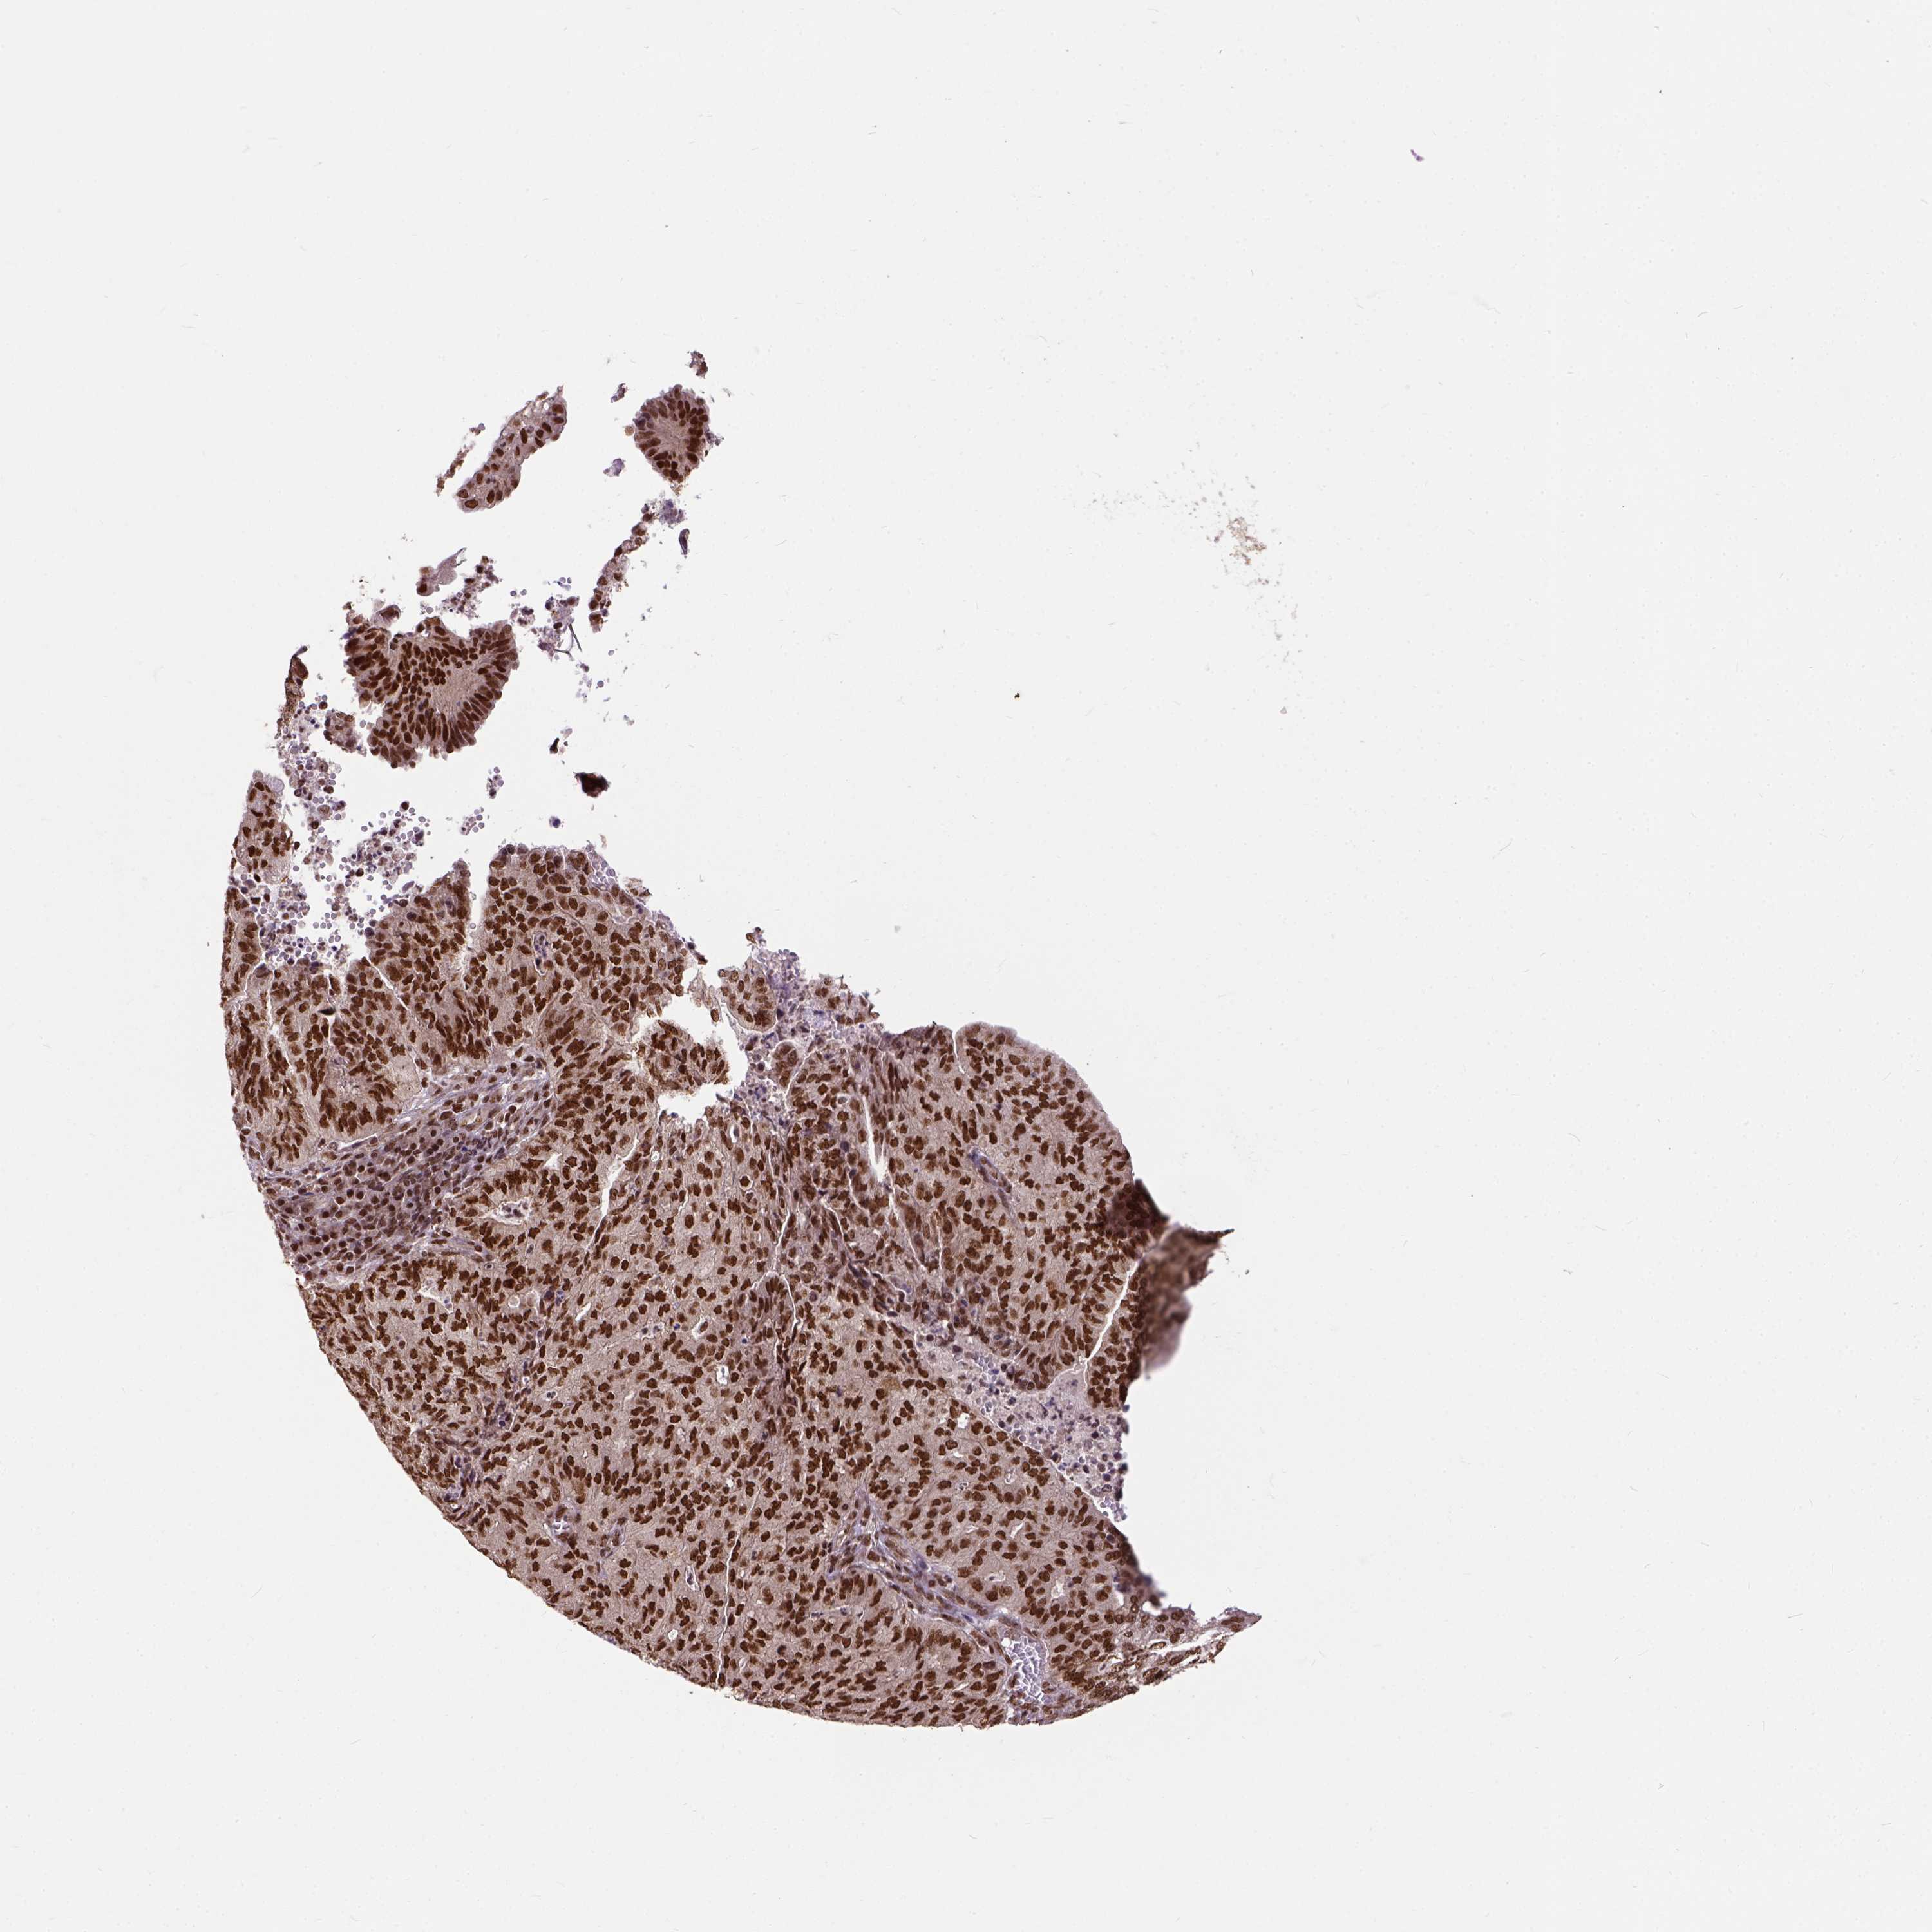

ENDOMETRIAL CANCER - Protein expressioni

A mouse-over function shows sample information and annotation data. Click on an image to view it in a full screen mode. Samples can be filtered based on level of antibody staining by selecting one or several of the following categories: high, medium, low and not detected. The assay and annotation is described here.

Note that samples used for immunohistochemistry by the Human Protein Atlas do not correspond to samples in the TCGA dataset.

Antibody stainingi

Antibody staining in the annotated cell types in the current human tissue is reported as not detected, low, medium, or high, based on conventional immunohistochemistry profiling in selected tissues. This score is based on the combination of the staining intensity and fraction of stained cells.

Each image is clickable and will lead to virtual microscopy that enables deeper exploration of all samples and also displays staining intensity scores, fraction scores and subcellular localization as well as patient and tissue information for each sample.

Antibody HPA021238

Antibody HPA062245

Antibody CAB069927

Staining

High

Medium

Low

Not detected

Intensity

Strong

Moderate

Weak

Negative

Quantity

>75%

75%-25%

<25%

None

Location

Nuclear

Cytoplasmic/membranous

Cytoplasmic/membranous,nuclear